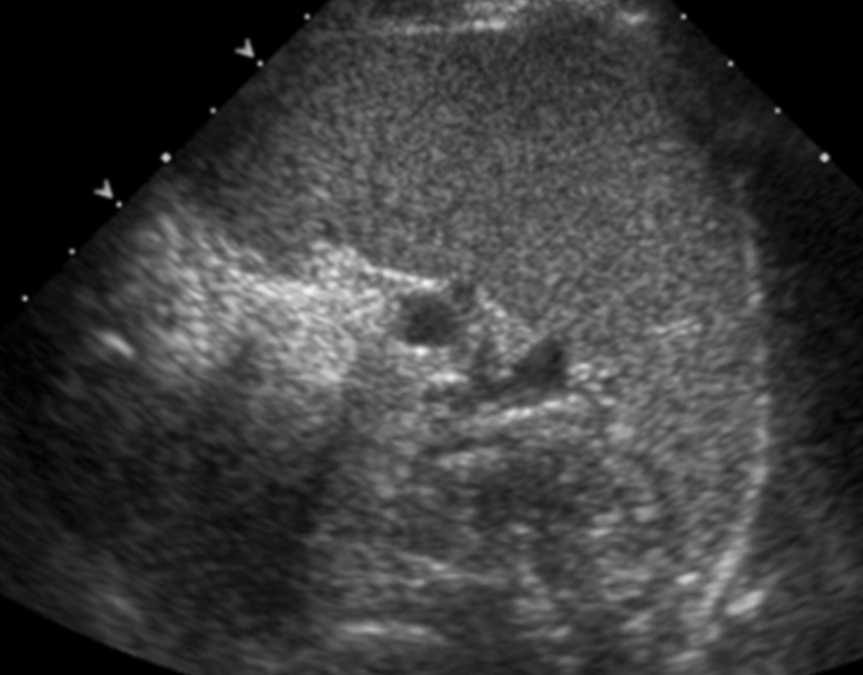

What is the sonographic appearance of an infarct?

Wedge/triangle shaped hypoechoic lesion

May become more echogenic with age

Sometimes difficult to differentiate from other possible masses such as hematoma